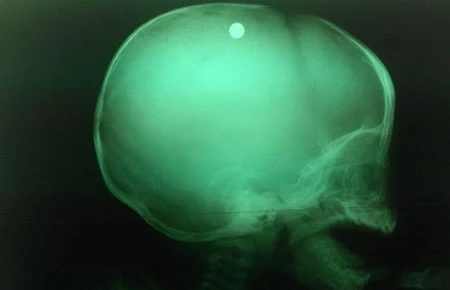

Phim chụp X-quang sọ cho thấy viên đạn vẫn còn nằm trong sọ của bé. Ảnh: WEBSITE BV NHI ĐỒNG 2

Các bác sĩ BV Nhi đồng 2 xác định đây là trường hợp vết thương sọ não cần phẫu thuật gấp vì phim chụp X-quang cho thấy viên đạn vẫn còn nằm trong sọ của bé. Sau năm tiếng phẫu thuật, các bác sĩ đã gắp ra được viên đạn tròn, đường kính khoảng 1 cm (viên bi trong bạc đạn - NV). Sau mổ, bé đã được chuyển xuống khoa hồi sức tích cực. Hiện bé đã có thể mở mắt nhưng vẫn còn phải thở máy, có những cơn co gồng và yếu nửa người bên trái.

BS Đặng Xuân Vinh, Phó khoa Ngoại thần kinh BV Nhi đồng 2, cho biết vị trí dị vật nằm trong nhu mô não (cách xương sọ 2 cm). Đạn được bắn thẳng vào não. Đường đi của viên đạn rất phức tạp nên nhu mô não của nạn nhân bị tàn phá nặng, kèm theo xuất huyết não. Cách mổ lấy viên đạn trong sọ não thông thường sẽ tàn phá rất nhiều nhu mô não của bé và di chứng về sau sẽ rất nặng nề. Do đó khi mở sọ, các bác sĩ phải dùng kính vi phẫu để làm sạch các mô não bị dơ, bị hư hại nhằm bảo tồn, tránh gây hại thêm các nhu mô não lân cận.